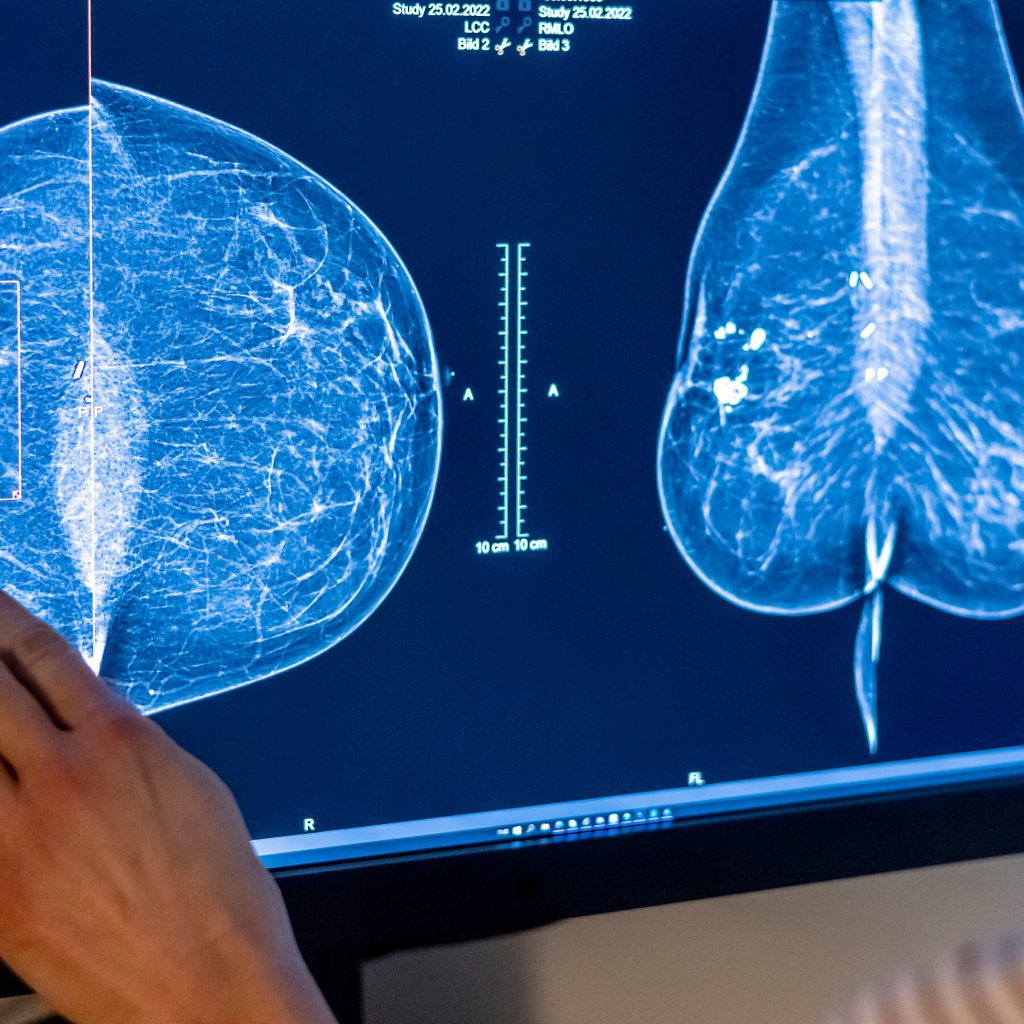

In Reversal, Expert Panel Recommends Breast Cancer Screening at 40

Some researchers said the advice did not go far enough. The panel also declined to recommend extra scans for women with dense breast tissue.Some researchers said the advice did not go far enough. The panel also declined to recommend extra scans for women with dense breast tissue. your-feed-science, Breast Cancer, Women and Girls, Disease Rates, Mammography, Cancer, Health Insurance and Managed Care, Age, Chronological, Ultrasonic Imaging and Sonograms, Preventive Medicine, United States Preventive Services Task Force Read More